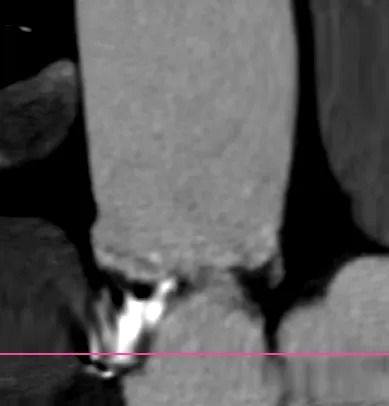

在这个病例中,我们能够看到升主对于瓣膜的推挤还是很大的,我们既往对于升主的长度有些人会用来评估同轴性,但是很多喜欢量中间来跟支架长度作对比,但实际上要量大弯侧边缘的到转弯地带的长度。

另外还可以看到二叶瓣的瓣膜植入进去,实际上瓣环那边是空的,虚拟瓣环没有任何锚定和封堵作用,实际上的锚定和封堵都是靠瓣上空间。二叶瓣的瓣膜选择需要抛弃依赖瓣环这个习惯。要综合考虑瓣上限制,过大oversize会导致框架扩张不充分(内折或者过度压缩)、瓣叶卷曲等影响血流动力学。笔者一直很反对过度的oversize。